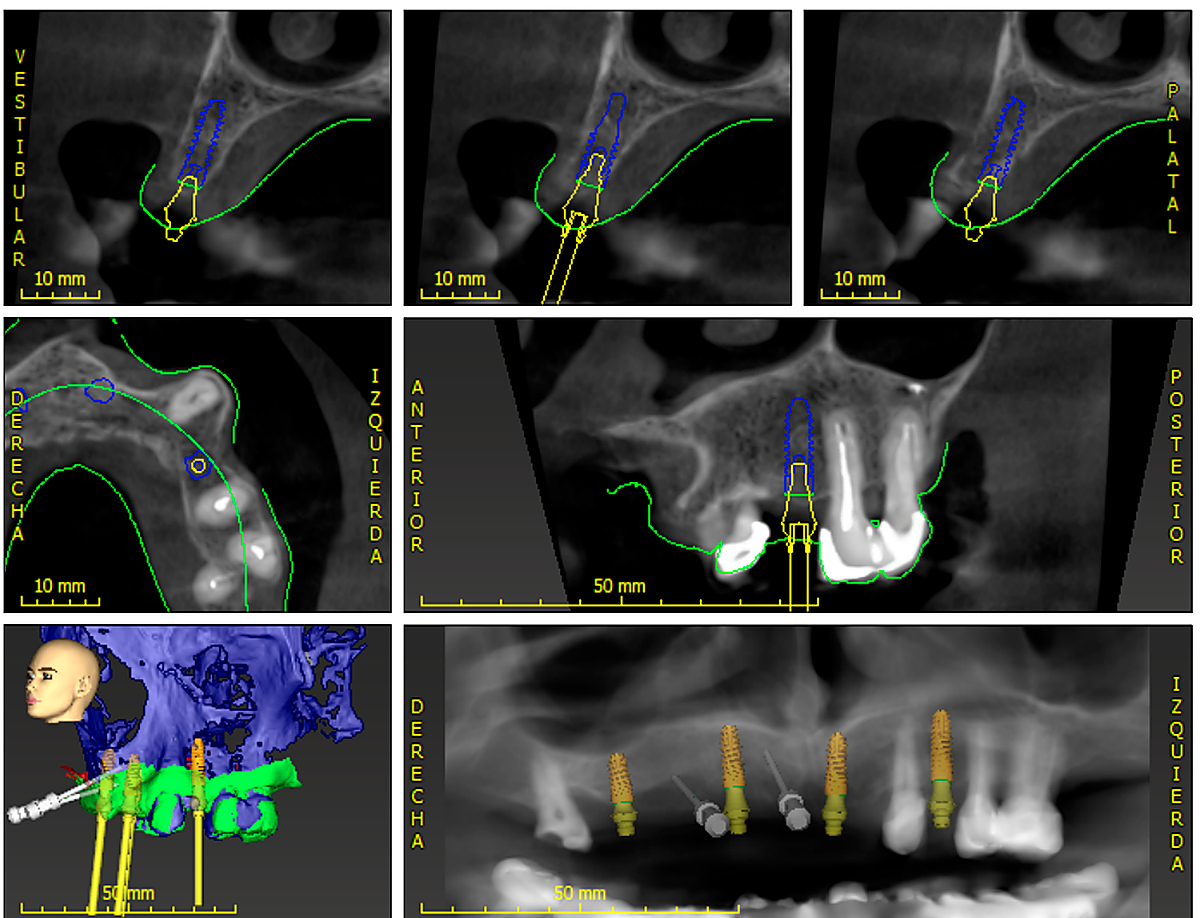

PASO 2. Planificación previa por ordenador de la colocación de los implantes.

Después de una primera valoración inicial para realizar el diagnóstico, el paciente se somete a un estudio 3D con un escáner intraoral que da como resultado un modelo a escala real de la boca. De esta forma, el doctor puede realizar en el ordenador una planificación previa sobre dónde colocará los implantes y cada paso que tendrá la intervención. Se trata de una planificación virtual que minimiza los riesgos. Cada movimiento se ejecuta en el ordenador ya que el estudio 3D permite conocer la anchura, altura y densidad del hueso donde se piensa colocar el implante.